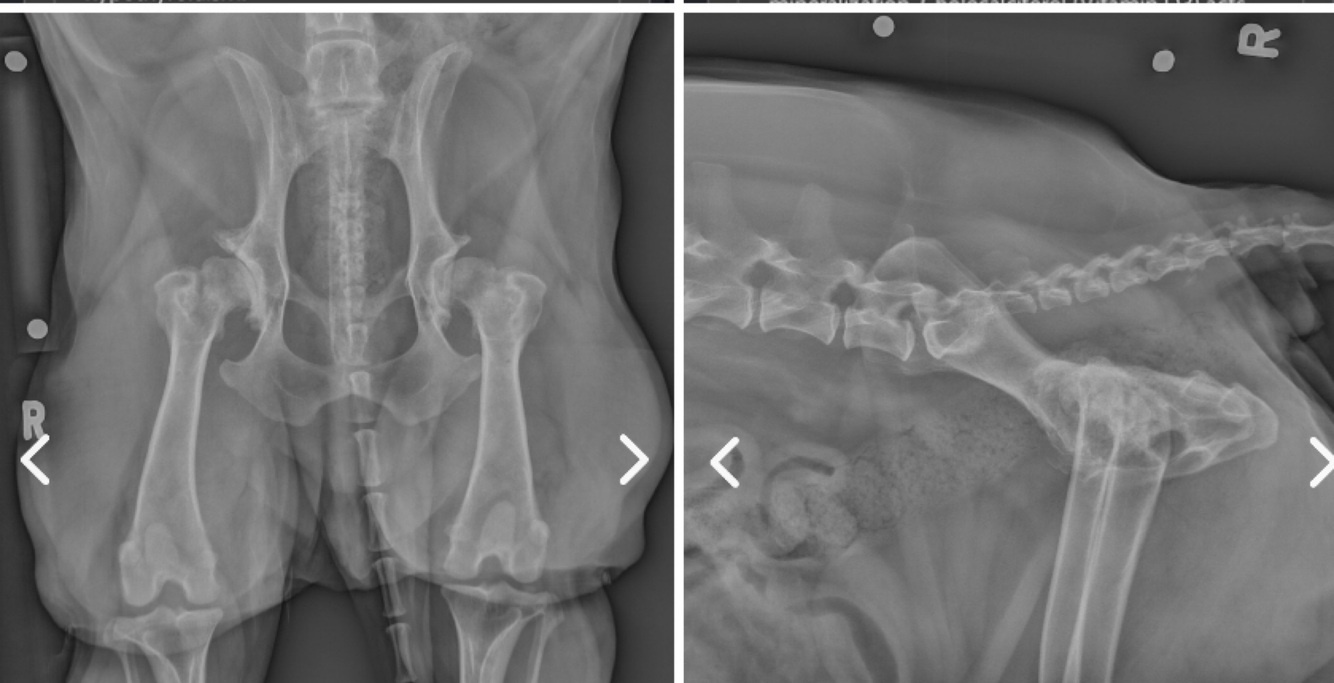

A 10 year old female spayed Dachshund presents for further evaluation of progressive lameness in the hind.

The owner notes that she has begun intermittently scuffing her hind limbs, has somewhat of a weak or drunken gait in the hind as she walks, and is having trouble rising. Given the answer choices below, what is the best treatment?

Answer: Dorsal laminectomy

This patient’s clinical signs are consistent with neurological deficits. Although you do not have all of the information necessary to reach a definitive diagnosis, you should have been able to deduce that this patient probably needs a dorsal laminectomy to relieve disc compression.

In order to definitively diagnose the condition you would want to proceed with a complete exam, basic bloodwork, and a CT or MRI of the lumbosacral region. Although this patient does exhibit evidence of hip dysplasia radiographically, the clinical signs are not characteristic of a dog with pain secondary to hip dysplasia. There is no indication of osteomyelitis on these radiographs and the clinical signs are not necessarily suggestive of osteomyelitis.

It is important not to skip ahead to image interpretation without carefully reading the question. Doing so in this case would likely lead you to select the incorrect answer.

Radiographs provided by Adrien Hesperian, DVM, MS, DACVR and University of Tennessee College of Veterinary Medicine